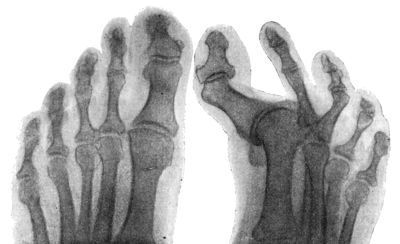

158.Radiogram of Hallux Varus or Pigeon-Toe298

159.Hallux Rigidus and Flexus in a Boy299